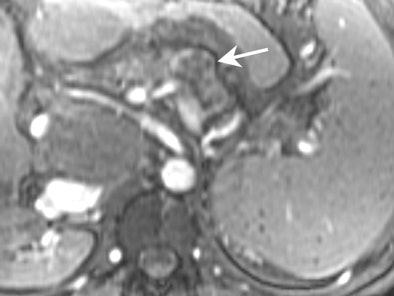

![]() |

| MRI demonstrating mucinous cystadenoma in tail of pancreas (arrow). On T2-weighted images the cyst fluid has high signal intensity similar to CSF. |